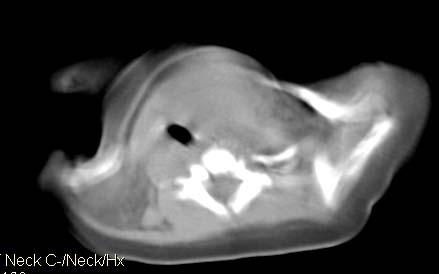

男,26天,发现左侧颈部包块5天,质较硬,患儿不哭不吵,无明显发热,头向右侧歪斜,其父母诉患儿出生时正常,昨天查血象wbc19.4×10的9次方/l,b超考虑来源于甲状腺的恶性肿瘤,我科认为肿块内有低密度区,而且病程发展较快,血象高,考虑炎性病变可能大。患儿年龄太小没做增强。请大家提出高见。

男,26天,发现左侧颈部包块5天,质较硬,患儿不哭不吵,无明显发热,头向右侧歪斜,其父母诉患儿出生时正常,昨天查血象wbc19.4×10的9次方/l,b超考虑来源于甲状腺的恶性肿瘤,我科认为肿块内有低密度区,而且病程发展较快,应该首先排除血肿,其次考虑感染

随访结果:炎症(患儿经过一星期抗炎治疗后颈部包块明显缩小,现已经正常)。